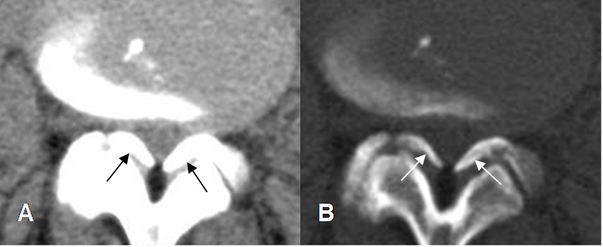

Fig 68. Articulaciones intervertebrales.

A: TAC axial y B: RM axial en T2. Hipertrofia de articulaciones intervertebrales, con disminución de los espacios interfacetarios.

Fig 69. Calcificación de los ligamentos amarillos.

A: TAC axial en ventana de tejido y B: TAC axial en ventana osea. Canal estrecho mixto, con hipertrofia de articulaciones intervertebrales y prominencia de los ligamentos amarillos, los cuales están calcificados.